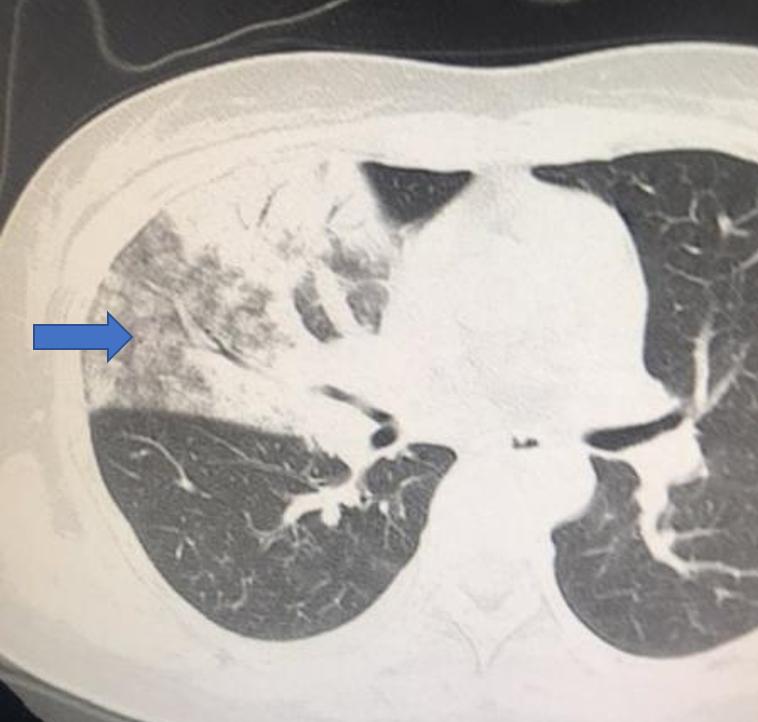

第二类,肺部感染性疾病。当由于外界致病微生物的入侵导致肺部感染时,会在病变部位引发炎症反应,白细胞、巨噬细胞等机体的免疫防御细胞会大量募集到病变部位与入侵者进行“战斗“。这些病原体本身的有形成分、各种炎症细胞及其碎片,以及脱落的组织细胞,都会积聚在肺泡内,当未将肺泡填满时,可以呈现为磨玻璃样阴影,而肺泡被完全填满时,则表现为实性阴影。所以,肺部感染性疾病,更常见到的是实性阴影与磨玻璃样阴影并存,磨玻璃样阴影一般位于实性阴影的外周。

右侧细菌性肺炎,箭头区域为肺磨玻璃样渗出影